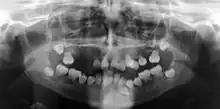

| Preoperative panoramic radiographs showing features of dentin dysplasia type I | |

Dentin dysplasia (DD) is a rare genetic developmental disorder affecting dentine production of the teeth, commonly exhibiting an autosomal dominant inheritance that causes malformation of the root. It affects both primary and permanent dentitions in approximately 1 in every 100,000 patients.[1] It is characterized by the presence of normal enamel but atypical dentin with abnormal pulpal morphology. Witkop[1] in 1972 classified DD into two types which are Type I (DD-1) is the radicular type, and type II (DD-2) is the coronal type. DD-1 has been further divided into 4 different subtypes (DD-1a,1b,1c,1d) based on the radiographic features.[2]

Type I: Radicular type

Radiographic feature

In other words, affected primary teeth usually have abnormal -shaped or shorter than normal roots. “Crescent/half-moon shaped” pulp chamber remnant in permanent teeth can be seen on x-rays. The roots may appear to be darker or radiolucent/pointy and short with apical constriction. Dentine is laid down abnormally and causes excessive growth within the pulp chamber. This will reduce the pulp space and eventually cause incomplete and total pulp chamber obliteration in permanent teeth.[12][13] Sometimes periapical pathology or cysts can be seen around the root apex.[11] Most cases of DD associated with peri-apical radiolucency/ pathology have been diagnosed as radicular cysts, but some of them have been as diagnosed peri-apical grauloma instead.[14]